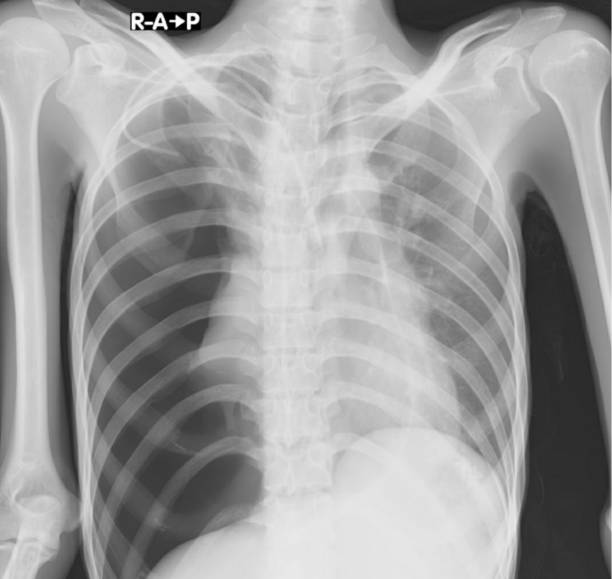

흉부 X선 검사

기흉이 의심되는 환자에게는 흉부 X선 검사를 실시하여 기흉이 있는지 확인할 수 있습니다. 이 방법은 비교적 쉽고 빠르게 기흉을 진단할 수 있습니다.